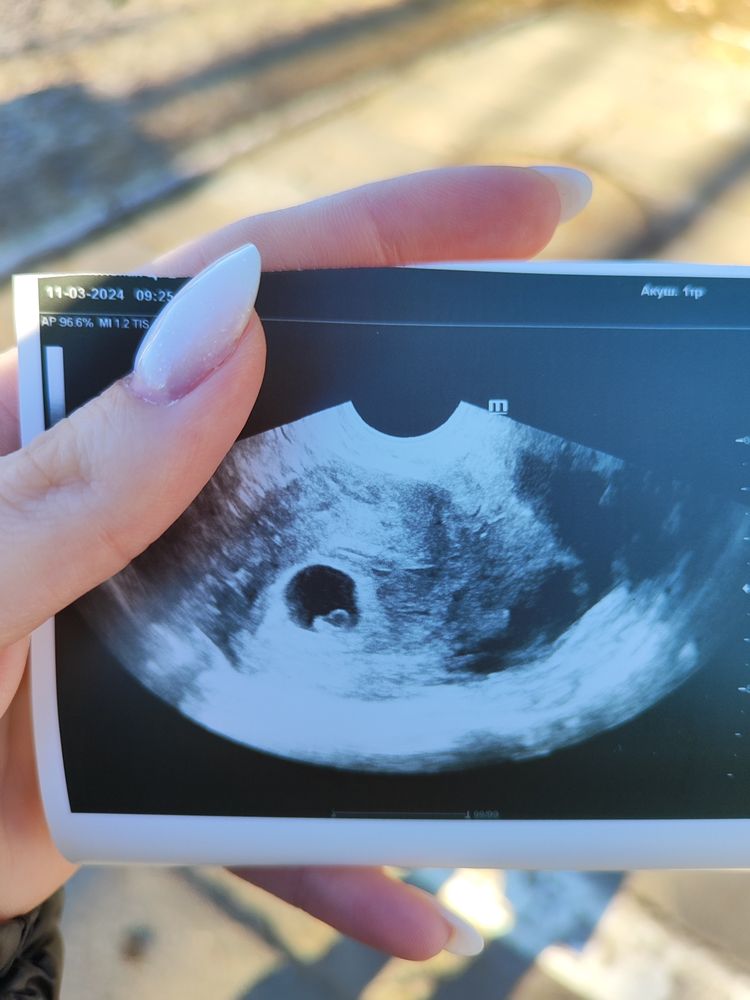

Anna Fort, акушерских 6 и 2) на УЗИ сказали 5, слышала методом Рамзи пол можно угадать)))) очень интересно!

"Будущая плацента " направлена ближе в мальчуковую сторону.

Damiana , я если честно хорион не смогла разглядеть ( Вы его справа или слева нашли? И определяем право/лево относительно снимка? Или УЗИ зеркалет?

Damiana , вы были правы)))) мальчик)))

Дашуля, на УЗИ сказали 5, акушерских 6 и 2